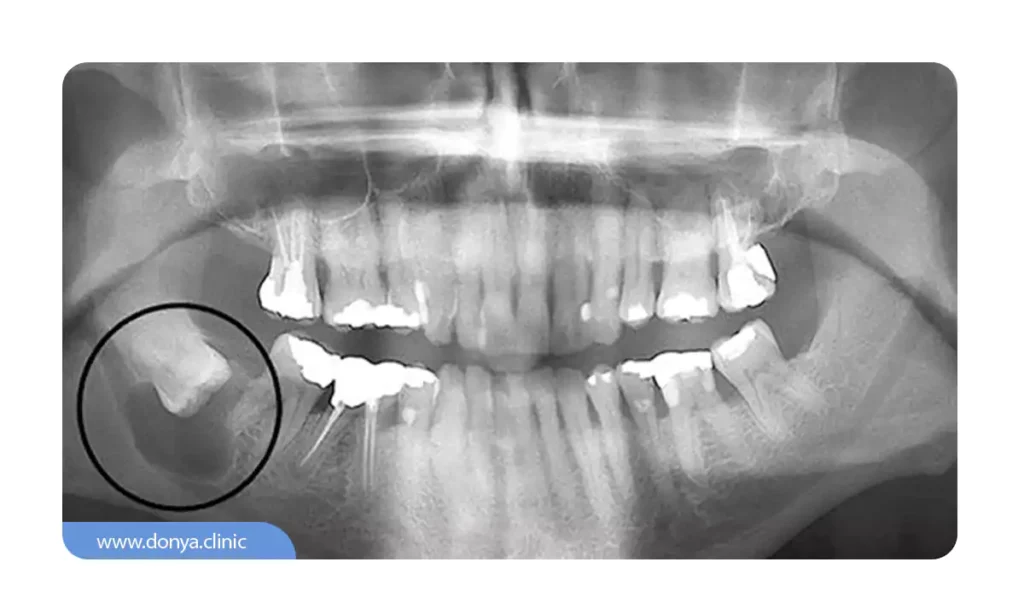

کیست های دندانی (Dentigerous Cysts)

کیستهای دنتیژروس که کیستهای فولیکولی نیز نامیده میشوند، در اطراف تاج دندانهای بیرون نیامده تشکیل میشوند. آنها زمانی رخ می دهند که رشد دندان با مشکل مواجه شود و منجر به تجمع مایع بین دندان و بافت اطراف آن شود.

کیست دندان عقل

کیست دندان عقل یک حالت پاتولوژیک است که معمولا در اطراف دندان عقل نهفته ایجاد می شود. این کیست ها می توانند به دلایل مختلفی تشکیل شوند و ممکن است باعث مشکلاتی برای فرد شوند. در ادامه، به برخی از جزئیات مربوط به آن می پردازیم:

علائم کیست دندان عقل

علائم مرتبط با این کیست می تواند شامل ناراحتی، درد، تورم و در موارد حاد، از دست دادن دندان باشد.این علائم معمولا در افراد بین ۲۰ تا ۳۰ سال بیشتر دیده می شود.

خطرات کیست دندان عقل

در موارد نادر، عدم درمان کیست می تواند منجر به ایجاد تومورهایی شود که می توانند به سایر قسمت های بدن گسترش یابند. این تومورها معمولا خوشخیم هستند اما می توانند به سرعت رشد کنند و نیاز به درمان فوری دارند.

درمان کیست دندان عقل

درمان این کیست ها معمولا از طریق جراحی انجام می شود. در برخی موارد، ممکن است نیاز به برداشتن بافت استخوان و لثه باشد و در موارد حادتر، کشیدن دندان های مجاور نیز مورد نیاز است.